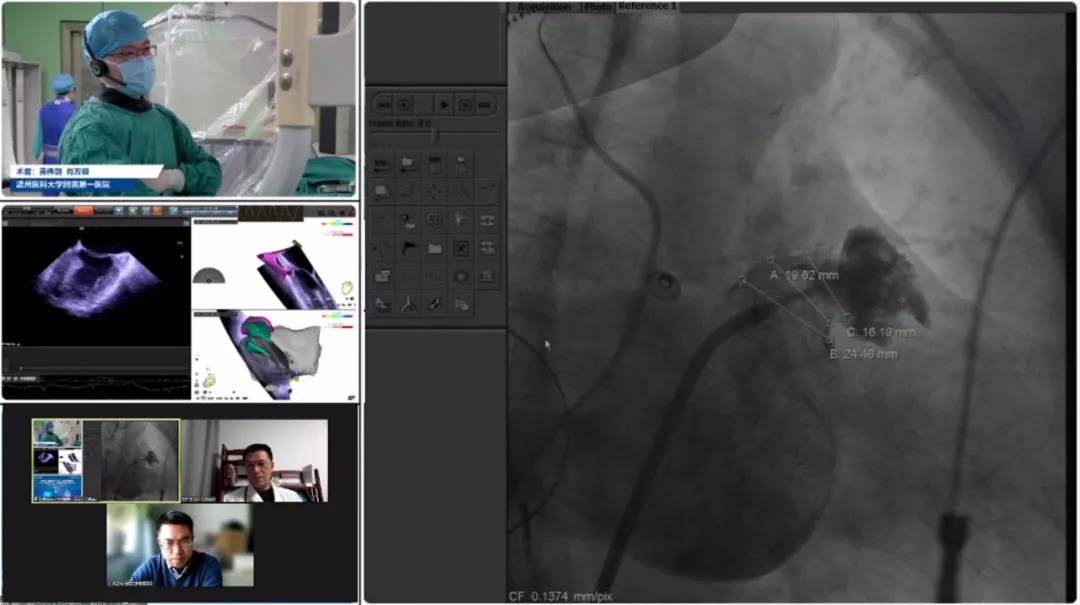

温州医科大学附属第一医院黄伟剑、肖方毅教授团队

患者女性,73岁,因体检发现心房颤动8月余入院,患持续性房颤、高血压及肝硬化史,CHA2DS2-VASC评分3分,HAS-BLED评分2分,拟在ICE引导下行LAmbre™左心耳封堵术。患者在局麻下行左心耳封堵术,左心耳测量锚定区约为16mm,封堵区约为24mm,选择LAmbre™型号为1832的小伞大盘封堵器进行植入。封堵器安全放置后,ICE下多角度观察未影响周围组织、未见心包积液、未见残余分流。LAmbre™独特的锚定机制能确保左心耳封堵器稳定牢固,牵拉测试十分稳定,符合COST原则,随后释放封堵器。